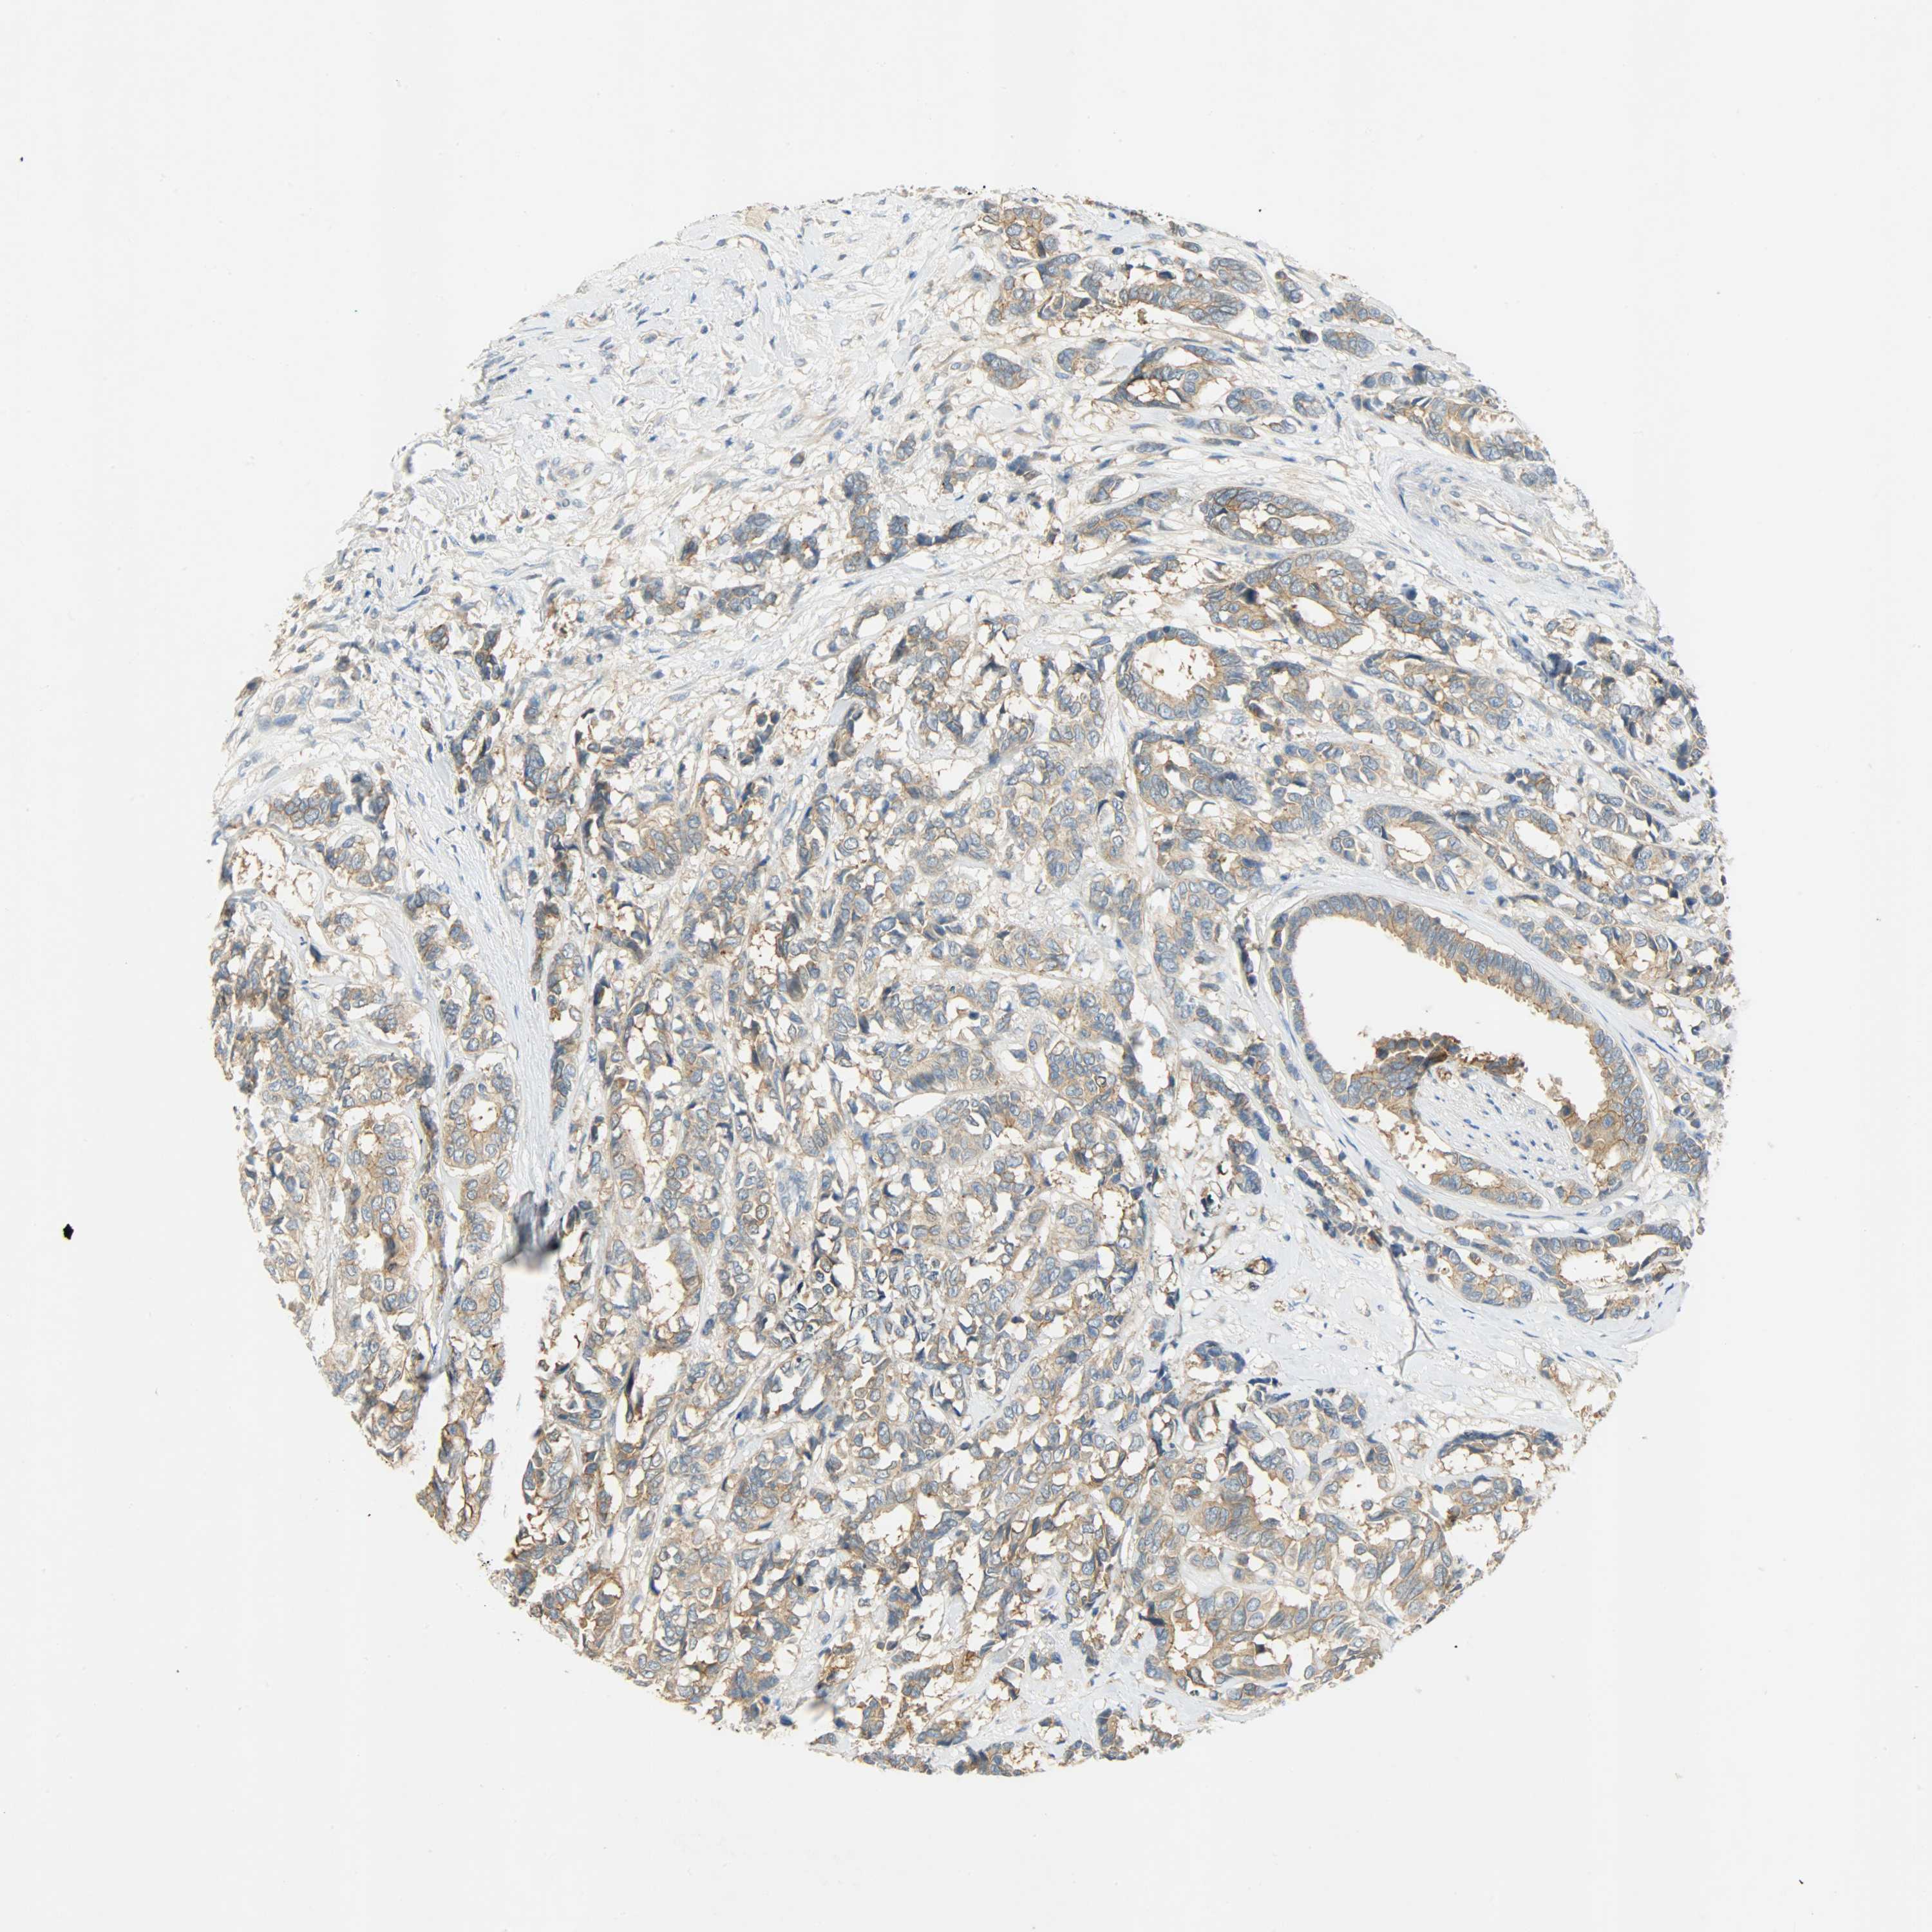

CANCER BREAST CANCER Show tissue menu

BRCA TCGA BRCA VALIDATION PROTEIN EXPRESSION